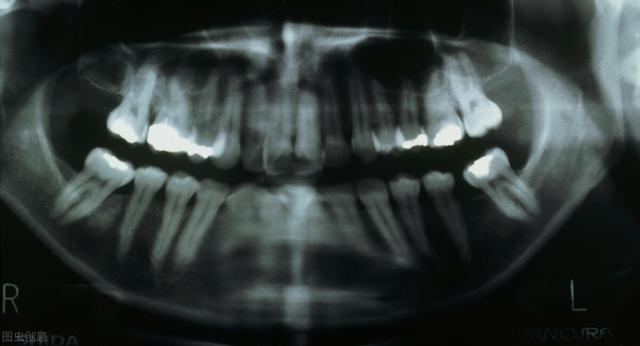

导致颌骨囊肿的病因主要可以分为牙源性和非牙源两类:1、 牙源性囊肿:多发颌骨大多与牙组织有关,病源主要分为以下几种:

·根尖周囊肿:根尖肉芽肿受到炎症的长时间刺激,会使牙周膜内部的上皮残余增生,增生后上皮组织病变液化就会一连 导致周围组织一直 渗透 液体,形成囊肿。

·始基囊肿:青少年乳恒牙患牙期发生的囊肿许多是始基囊肿;上皮组织在受到炎症或外伤刺激时,成釉器星网状层病变会渗透 液体且无法倾轧 ,逐步形成单囊或多囊。

·滤泡囊肿:病发部位与年岁 有关,与始基囊肿类似也多发于替牙期;牙冠或者牙根形成之后所余釉上皮渗透 液体,形成囊肿,囊肿内可能会含有一颗或多颗牙胚,故也被称为含牙囊肿。

·角化囊肿 :多发病与20至40岁青壮年时期,泉源 于原始的牙板加入或者是牙胚,以是 大部门患者牙齿排序不齐,有缺牙少牙的症状;囊肿生长缓慢,与其他囊内清亮液体差异的是,角化囊肿积液泛起白色或者黄色。